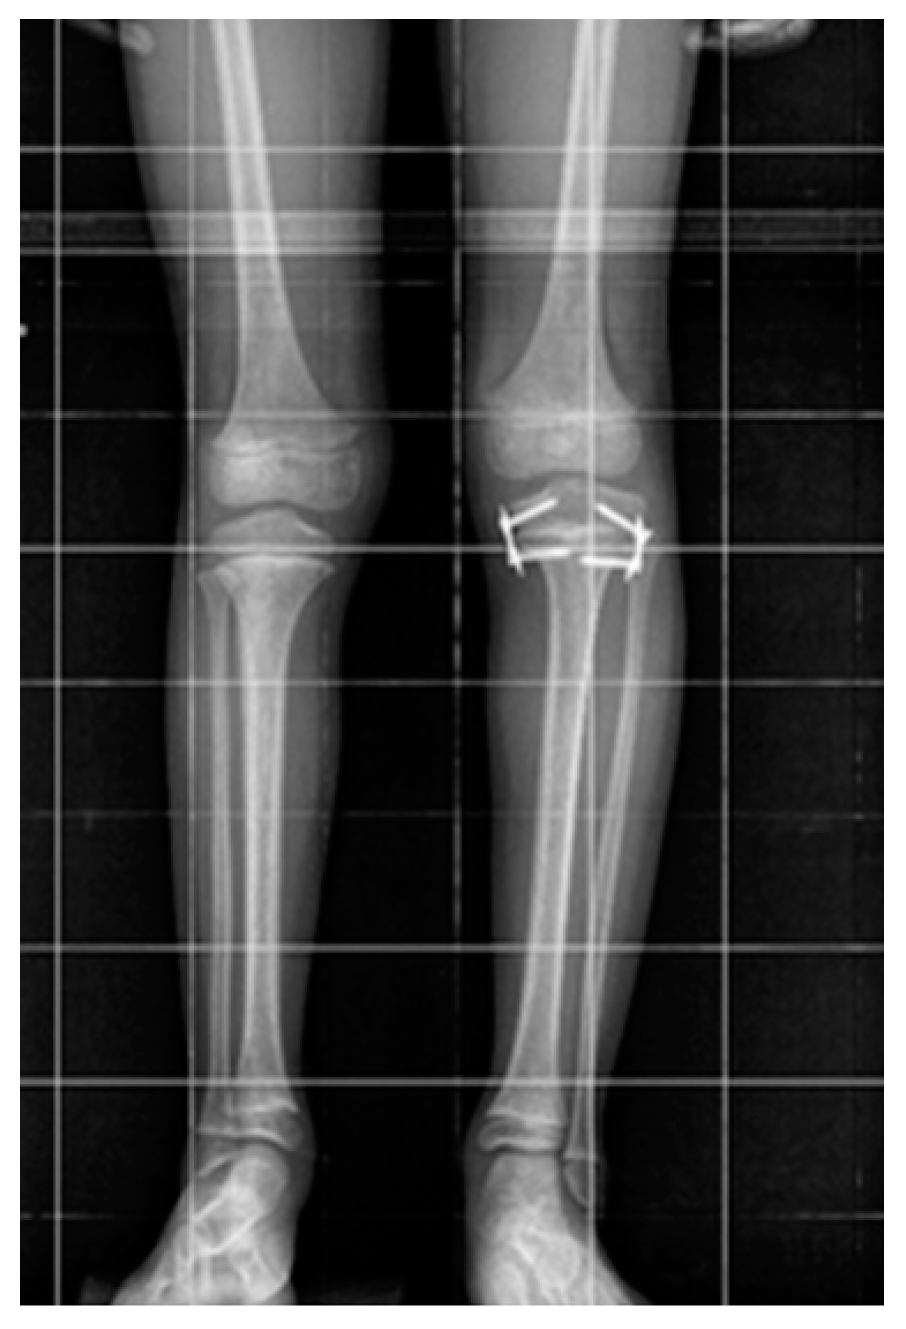

Limb Axis Disorder During Leg Length Discrepancy Treatment with Temporary Epiphysiodesis Using Eight-Plate Implants

- Starobrat, G.; Danielewicz, A.; Szponder, T.; Wójciak, M.; Sowa, I.; Różańska-Boczula, M.; Latalski, M. The Influence of Temporary Epiphysiodesis of the Proximal End of the Tibia on the Shape of the Knee Joint in Children Treated for Leg Length Discrepancy. J. Clin. Med. 2024, 13, 1458. [Google Scholar] [CrossRef]